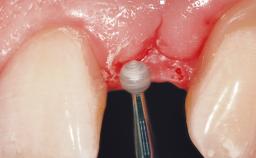

A 30-year-old female patient had lost tooth 21 and was referred to our clinic for consultation and treatment. Due to advanced apical infection, tooth 21 had been extracted two months earlier at another clinic and an acrylic-resin tooth had been bonded to the adjacent teeth. The patient desired implant treatment to avoid any damage to the adjacent natural teeth. While the patient had no history of any systemic disorder, she was a heavy smoker and exhibited medium to advanced periodontitis in the entire jaw. After the initial treatment to achieve a pocket probing depth of less than 4 mm and no bleeding on probing, a decrease in the height of the papillae mesial and distal to the extraction site and overall gingival recession were observed.

Soft Tissue Grafting Simultaneous

Soft Tissue Anatomy Intact Defective

Soft Tissue Contour and Volume Slightly compromised